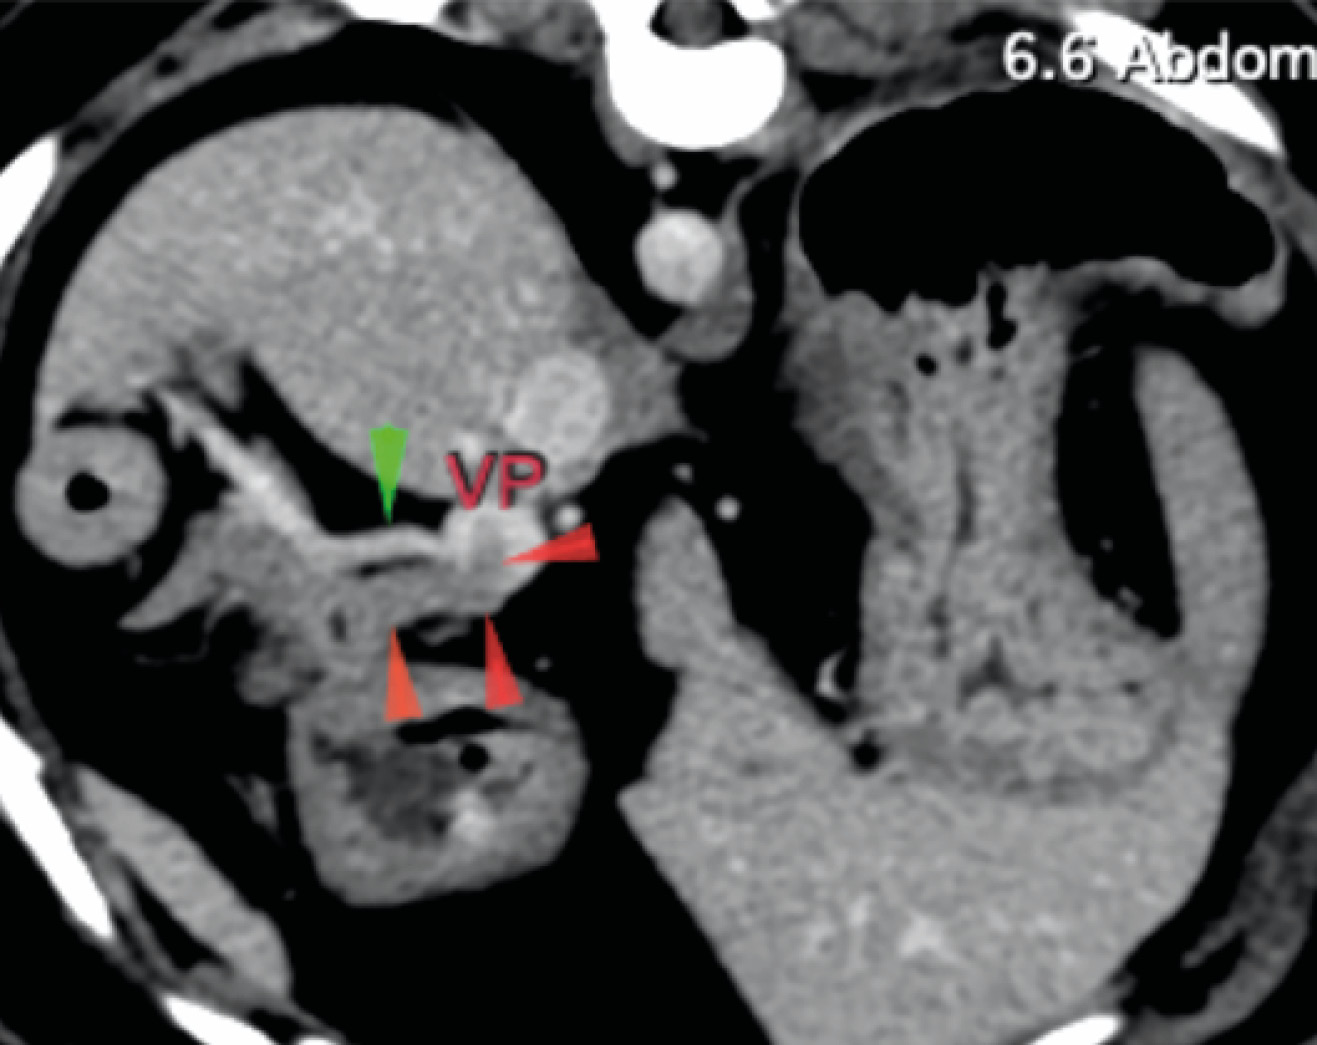

La ecografía abdominal reveló una lesión en el parénquima del cuerpo pancreático con posible invasión vascular a la vena porta. Una TC abdominal con contraste evidenció la lesión asociada al cuerpo del páncreas, con invasión de la vena porta (imágenes 1A y 1B), junto con la presencia incidental de un cuerpo extraño gástrico y signos de enfermedad degenerativa torácica y lumbosacra. Se realizó la extracción endoscópica del cuerpo extraño mediante gastroscopia durante el procedimiento anestésico.

Se realizó una laparotomía exploratoria por línea media ventral y se observó un nódulo en el cuerpo del páncreas con invasión de un trombo tumoral en la vena porta y otro nódulo de menor tamaño en el lóbulo izquierdo (imágenes 2A y 2B).

Actualmente, la TC se considera la técnica de referencia para la detección y localización preoperatoria de insulinomas y metástasis. La ecografía resultaría útil si se consideran apropiados los aspirados o biopsias por aspiración con aguja fina ecoguiados de cualquier lesión hepática, ganglios linfáticos regionales y ganglios linfáticos agrandados detectados en la CT para facilitar la estadificación precisa de la TNM preoperatoria.

En nuestro caso, la ecografía abdominal identificó una lesión en el parénquima del cuerpo pancreático con posible invasión vascular y nódulos linfáticos aumentados de tamaño (aunque no metastásicos); estos hallazgos se confirmaron en la TC. Sin embargo, la enfermedad metastásica se evaluó mediante la inspección macroscópica del hígado y la localización de un segundo nódulo en el lóbulo pancreático izquierdo, que fue reseccionado.